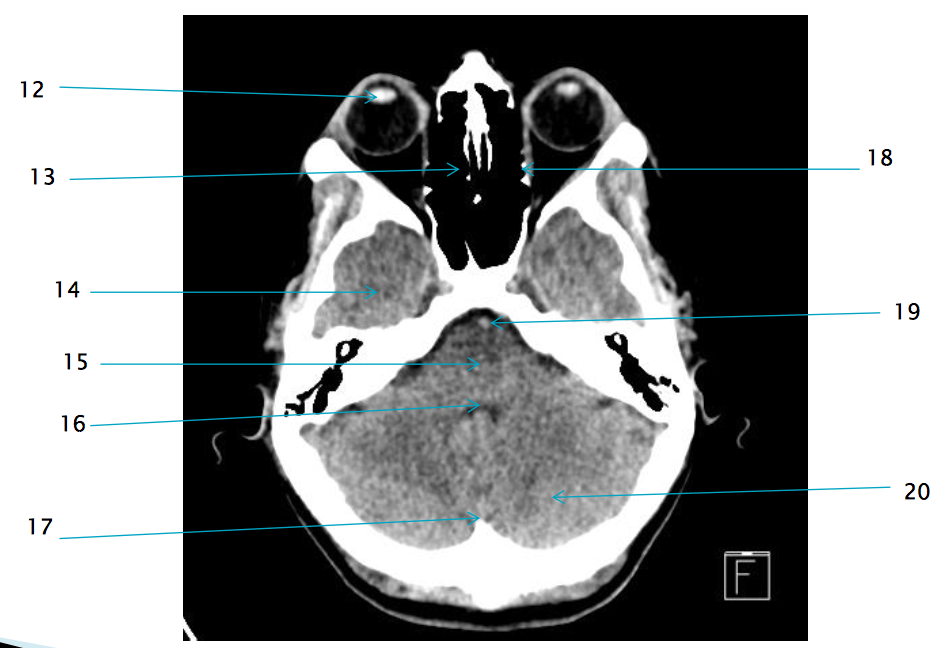

12

lens of R eye

13

ethmoid air cells R

21

R zygomatic bone

19

basilar artery